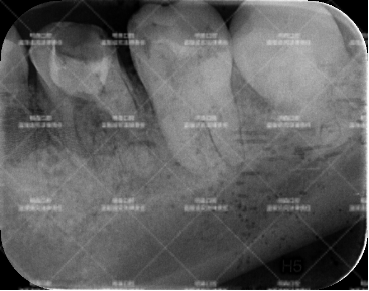

患者术前CT照

当时我听完患者的故事,赶紧让他拍了CT片仔细检查一遍,都这么多年了......没点症状就不太符合医学常识了。CT检查显示:

· 充填物边缘有继发龋

· 显示根管填充不到位,根尖还有阴影,说明有慢性炎症。